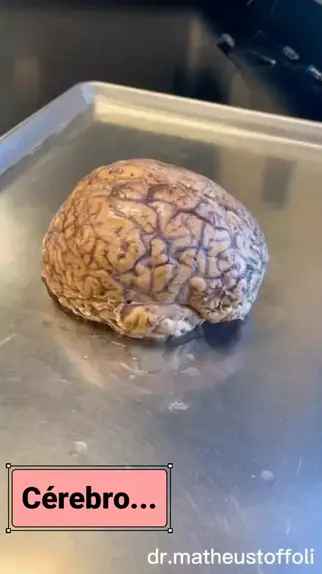

Um pouco da nossa aula de Anatomia. Professor Lucas. #meggacursos #Lucas #necropsiaeeu

Chegou a tão desafiadora Aula de Anatomia Humana... #necropsiaeeu #aprender #estudar #necropsia

Sistema Muscular. Um pouco da nossa aula no dia 12/02/2022. #sistemamuscular #necropsiaeeu #fajackefotografia #curiosidades #professorgermano #